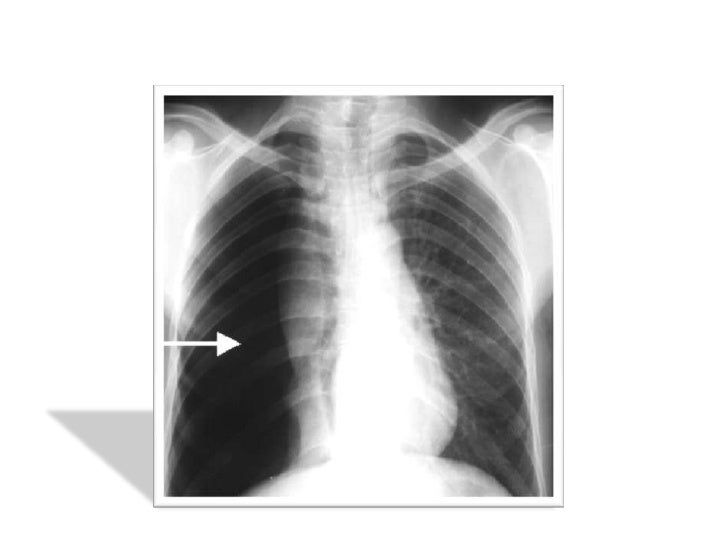

Emphyseme A Patient De 78 Ans Aux Antecedents D Emphyseme Pulmonaire Download Scientific Diagram

Figure 1 Thorax

Suivi D Une Bpco Stade Iv Chez Un Patient De 57 Ans Les Bulles Download Scientific Diagram